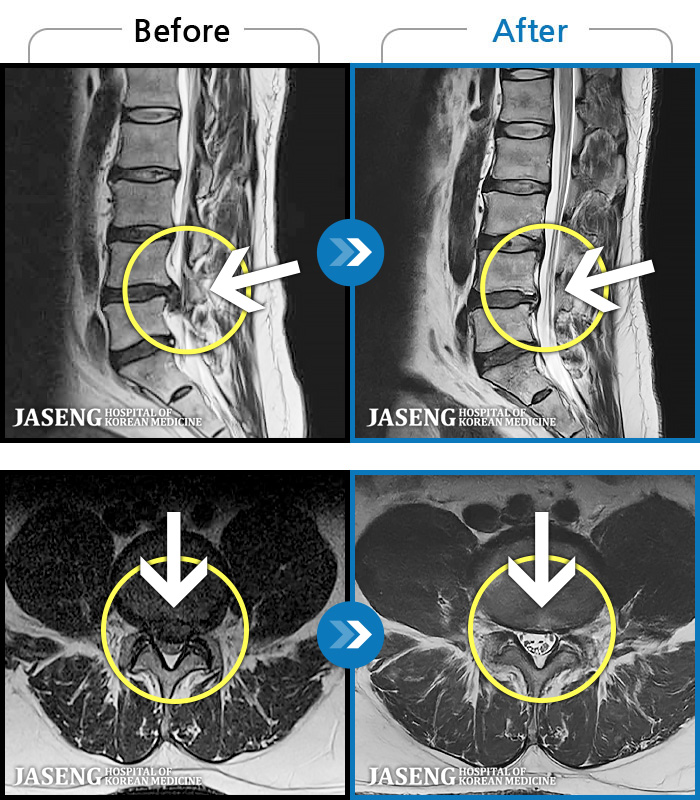

MRI ġ

119 MRI ũ ʸ Ȯϼ.

[Կñ:24.01.30~24.07.09]

[_㸮ũ] ٸ ؼ ɾٴϱ

No.119

ȸ 599

2024.12.24